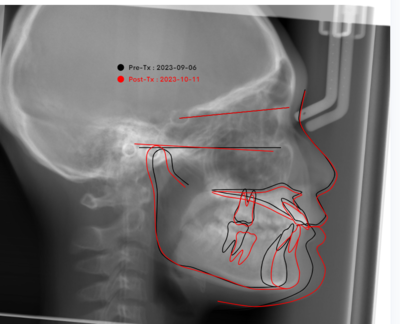

横から撮影した頭部の規格写真(セファロといいます)で通常の咬み方のセファロと下顎を前に出したセファロを重ねてみても、プロファイルは変わりなくイーラインの中に入っています。この患者さんは、下顎が奥に下がっているタイプの出っ歯ということになります。

セファロ写真を撮影し、分析をして評価・診断がとても大切になってきます。